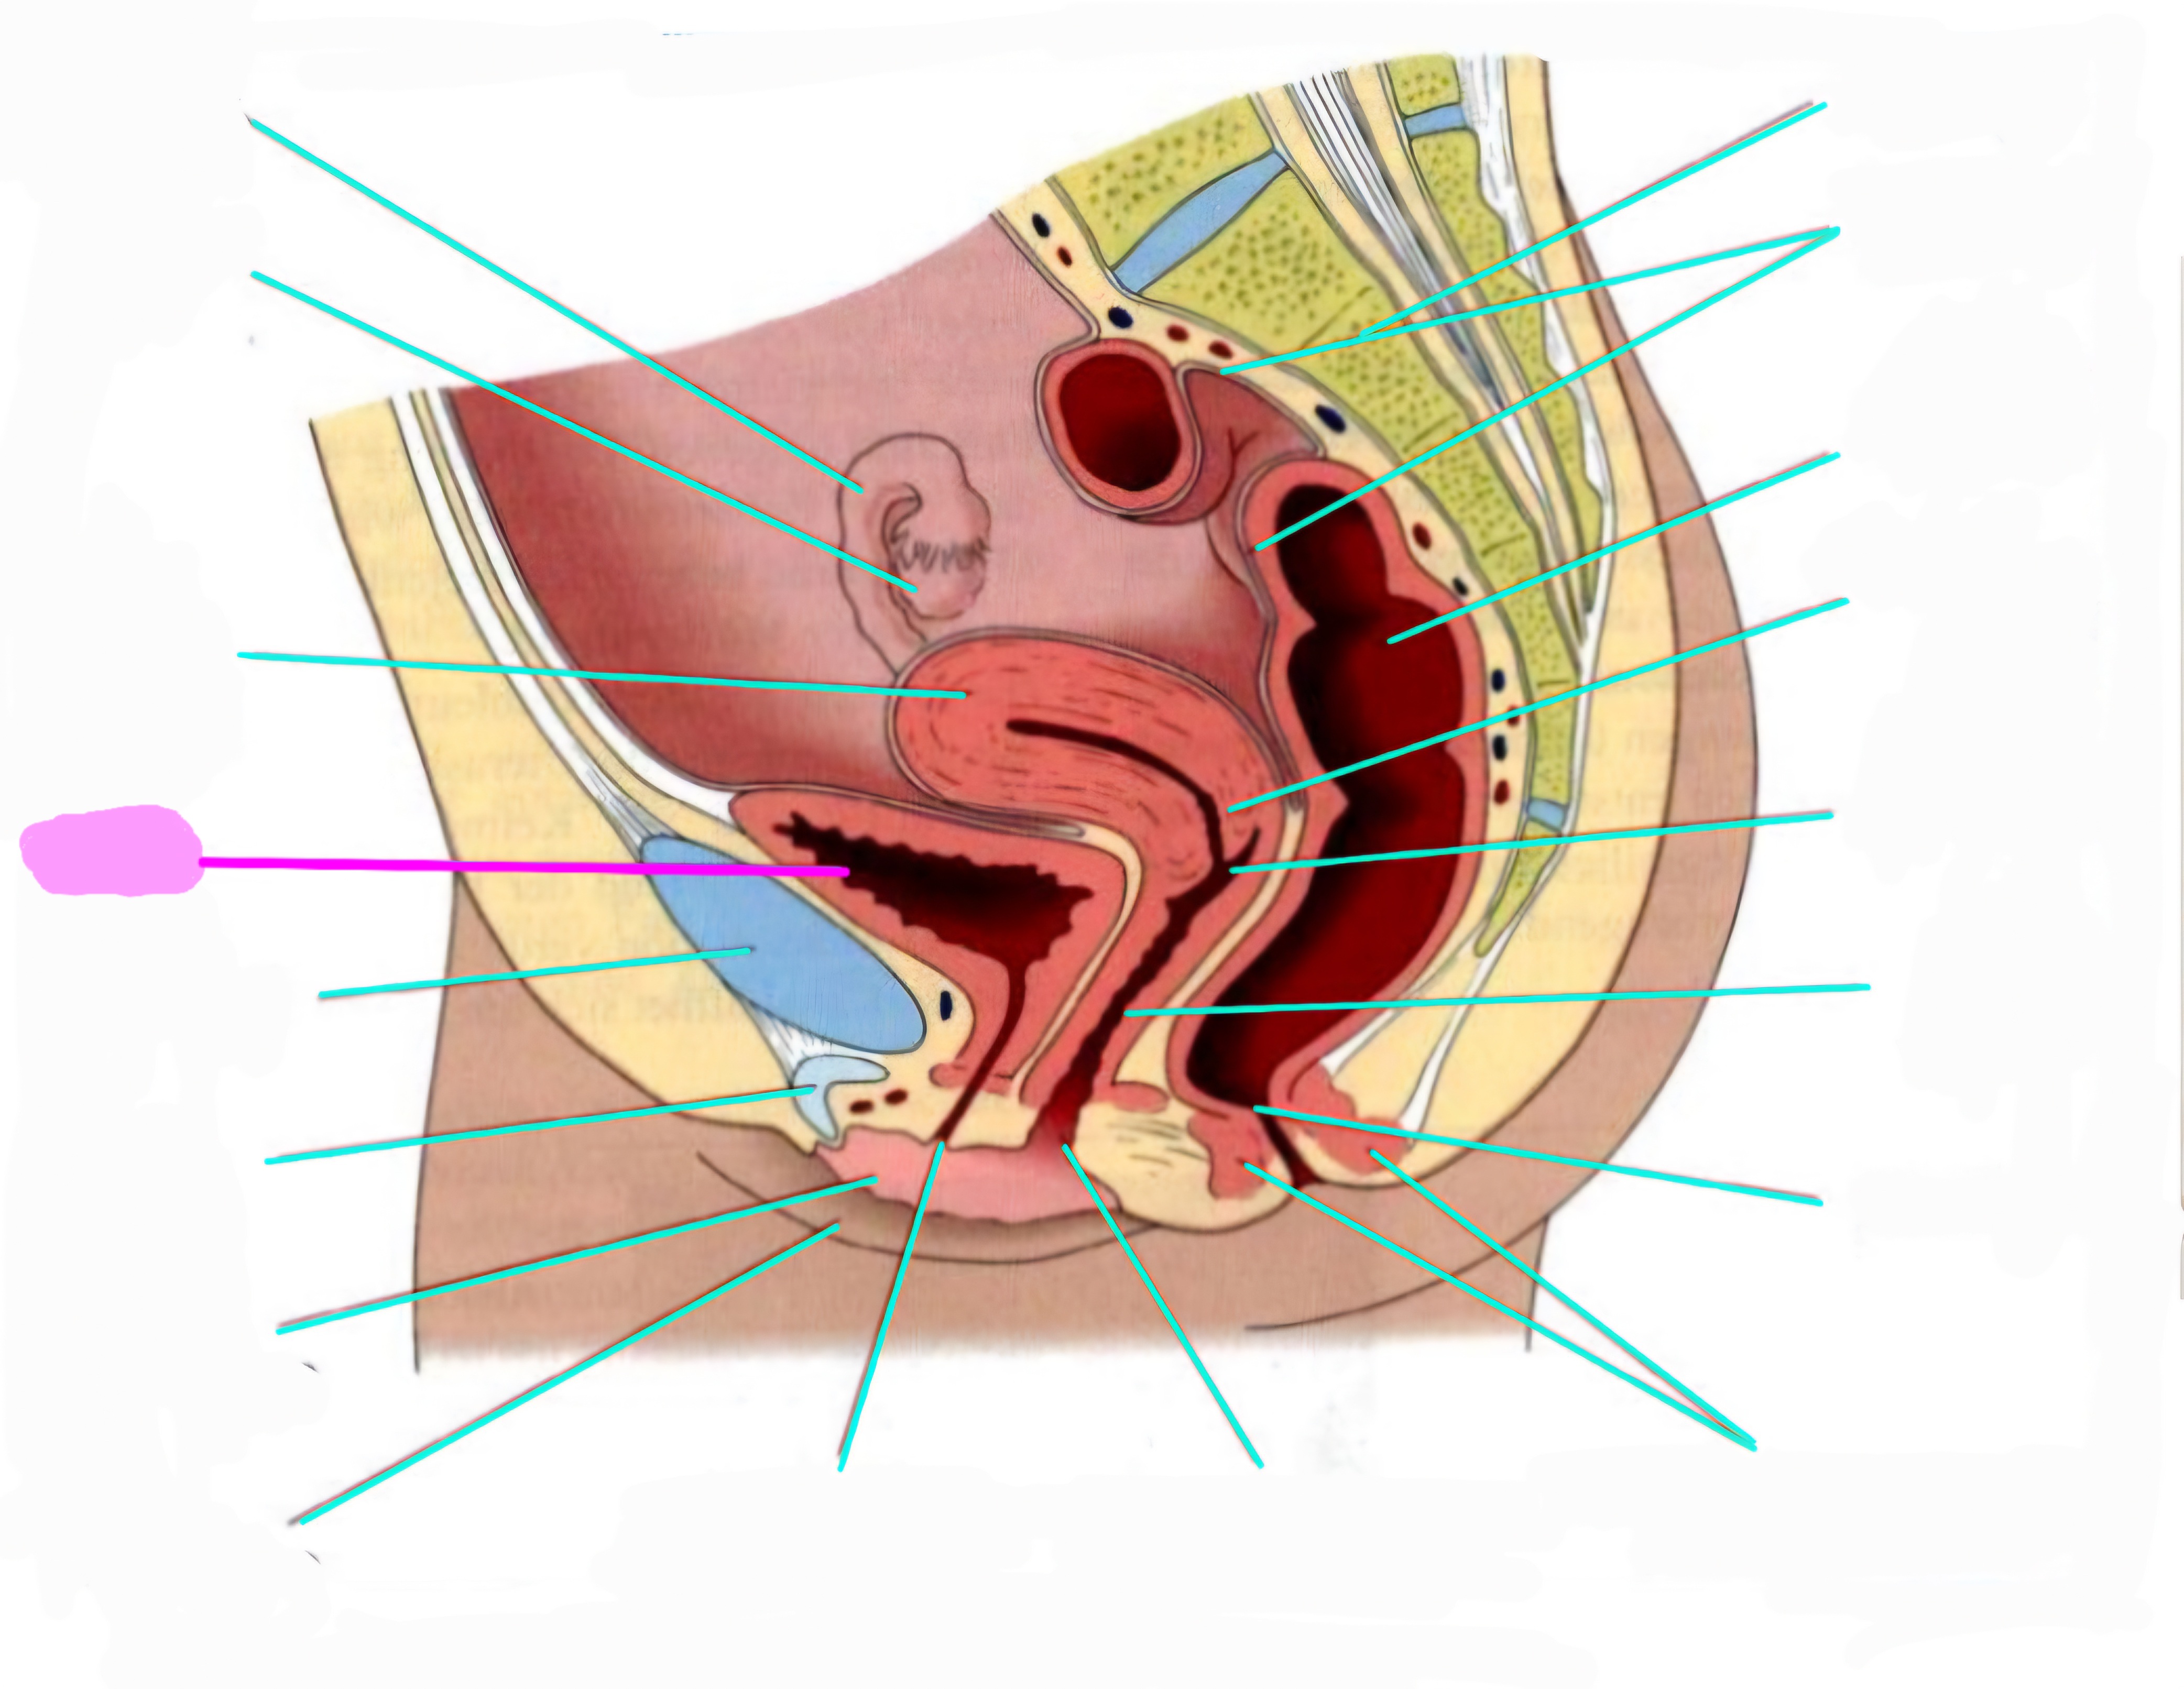

wbl. genital Anatomie

19 Terms

Tubea uterina (Eileiter)

Ovar (Eierstock)

Uterus (Gebärmutter)

Vesica Urinaria (Harnblase)

Symphyse

Klitoris

Labia minor pudendi (kleine schamlippen)

Labia Majoran pudendi (große Schamlippe)

Urethra (Harnröhre)

Introitus vaginae (Scheideneingang)

Sphincter ani externes (äußere Afterschließmuskel)

Anus (After)

Vagina (Scheide)

Portio (äußerer Muttermund)

Rektum (Mastdarm)

Zervix (Gebärmutterhals)

Peritoneum (Bauchfell)

Os sacrum (Kreuzbein)